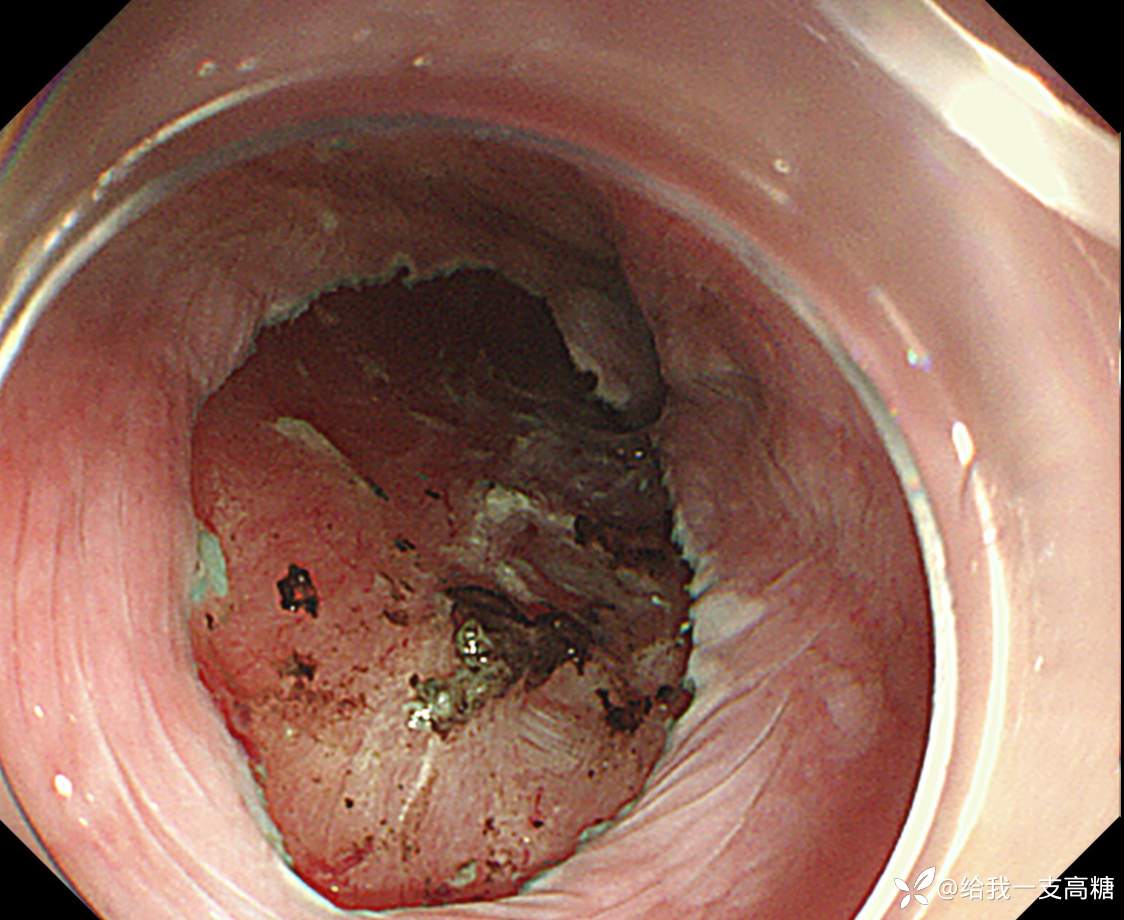

食管早癌ESD一例

门诊体检行胃镜见食管中段黏膜粗糙,活检提示高级别,鳞状细胞为主

NBI下见局部IPCL B1

完整剥离、固定

术后病理局部鳞状上皮呈高级别异型增生